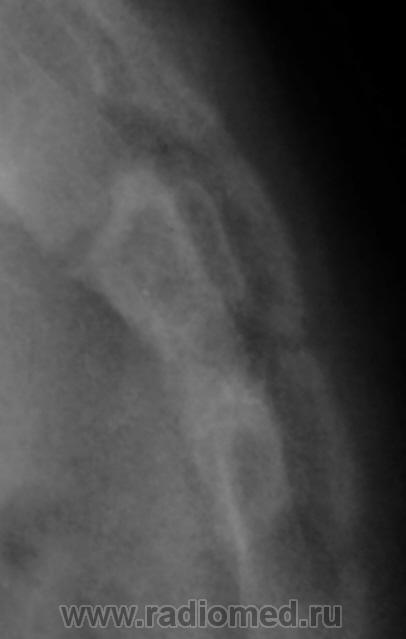

Ребенок направлен хирургом на рентгенографию крестца и копчика, Накануне ребенок упал. Приводится только боковая рентгенограмма, так как рентгенограмма, выполненная в прямой проекции не информативна.

Вопрос. Есть перелом или нет перелома?

Перелома нет

Уважаемый Валентин Львович! Наличия костно-травматических изменений со стороны объекта исследования не выявлено. Кстати, у меня редко получаются такие красивые рентгенограммы крестца и копчика.

Валентин Львович! Мне видится межпозвонковый промежуток. Смещение по ширине отсутствует. Возможно такой вариант развития. Все таки изолированно сломать крестец у ребенка сложно.

Я тоже костно-травматических изменений не вижу.

Согласен с Ермолаевым, это межпозвонковый промежуток.